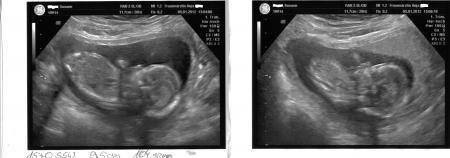

Meine macht bei dieser schwangerschaft leider nicht jedes mal ultraschall (hat sie bei meiner 1 gemacht aber da war sie auch in einer anderen praxis) am donnerstag hatte ich einen termin da hätte sie keinen ultraschall gemacht aber ich wollte es und habe 15 euro zahlen müssen und habe 3 bilder bekommen aber ich werde es jetzt immer machen wenn kein ultraschall ist

Bild zu